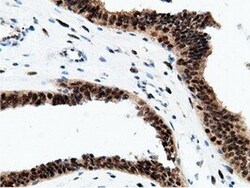

- Immunohistochemical staining of paraffin-embedded human prostate tissue within the normal limits using anti-EPM2AIP1 mouse monoclonal antibody. (Heat-induced epitope retrieval by 10mM citric buffer, pH6.0, 100°C for 10min, TA501797)